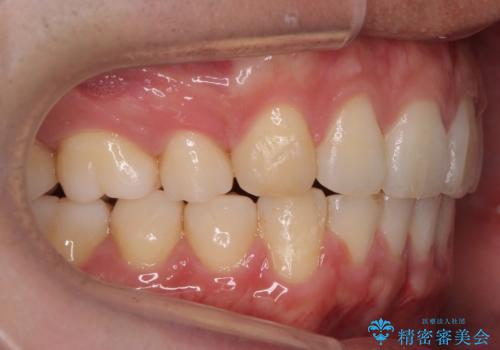

出っ歯の治療 インビザラインで抜歯矯正 親知らずを使用した矯正

- 出っ歯を主訴に来院。

上の小臼歯を2本抜歯しています。

そのかわり、上の親知らずを生かしており、歯の本数は減っていません。

時間はかかりましたがしっかり前歯を下げて治療しています。